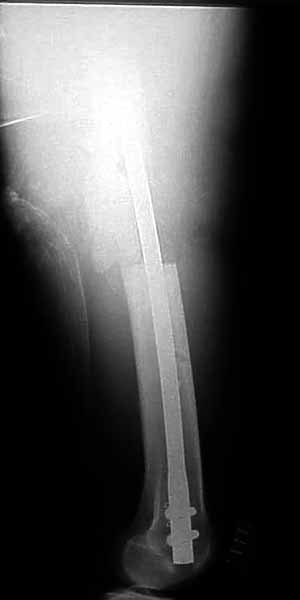

30 y/o man in head-on MVA 12/22/03 sustaining grade II open left femoral midshaft fracture (treated with appropriate staged debridement and retrograde statically locked IM nail), left lateral split tibial plateau fracture (treated with reduction and percutaneous cannulated screw fixation) and comminuted left femoral neck fracture (treated with open reduction and non-compression screw fixation). All initial treatment at another institution and patient recently came to me for follow-up care (he was travelling out of town when he was injured). He has a large (7cm) defect of lateral half of femoral shaft fracture which I plan to pack with a ton of bone graft next week (open fracture site soft tissues healed nicely without sign of infection).

Only small part of femoral shaft fracture visible on one xray. I would be interested in seeing xrays of the shaft fracture. I would be hesitant about bone grafting the femoral shaft fracture early. It might heal. Femoral neck fracture is going to be a problem. I agree, in varus and almost appears with some distraction at the fracture site. I do not think anything now will significantly increase the chance of salvage. I would suggest observation over a reasonable period of time while on crutches, documentation of healing or lack of healing with CT or tomogram (hard to get as the machines are fewer and fewer), then definitive treatment of what is left at the hip. Not an agressive approach but one that gives a 30 year old a chance to heal given how he was initially treated.

I agree that most femoral shaft fractures (even with defects) don't need grafting, but without inclusive films it's difficult to make an opinion regarding this shaft defect.

The issue of the shaft is harder to tell from the images, but could be addressed concurrently or seperately, based on dedicated imaging.

TF> He has a large (7cm) defect of lateral half of femoral shaft fracture which I plan to pack with a ton of bone graft next week

I agree with Bryan Neal that probably no need to hurry with this.